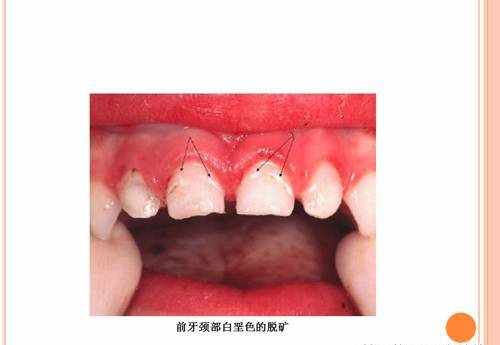

白斑

牙垢沉积在牙齿表面,牙齿表面珐琅质被牙垢中的细菌消化糖后,排泄出来的酸溶解,就发生脱矿了。

牙齿中的钙减少了,色泽就变成白粉笔色(白琧)感觉了。

因为凡事有利必有弊,若牙齿在发育期间暴露在过高浓度氟化物中,牙齿发育会受到影响,引起氟斑牙(如下图)。

通过涂氟保护漆,让出现了脱矿的牙齿(早期蛀牙的表现)得到了明显的修复。